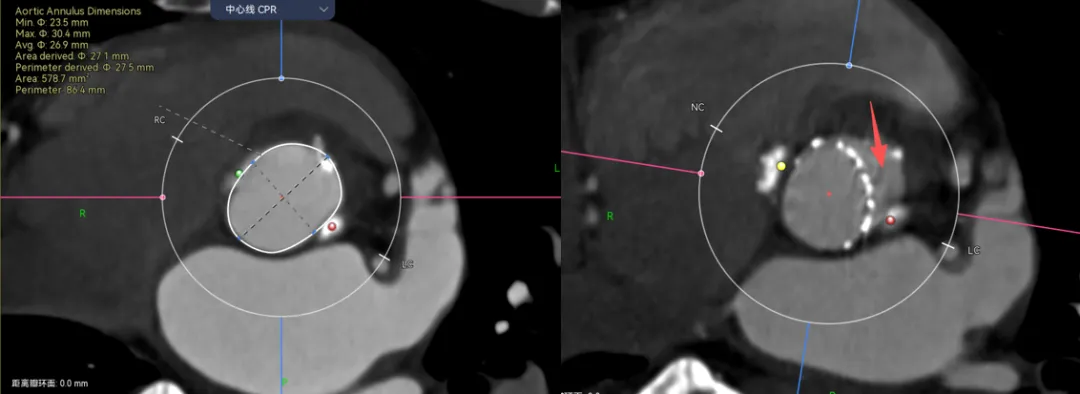

举个例子,病例-5,Type1的单边钙化,延伸到LVOT,瓣环这里笔者认为是因为把钙化避开的,因为他会对瓣膜有推挤作用。有些人则不会避开,这样瓣环会比预估的要大很多。

画法1-把钙化圈进去,瓣环径28。画法2-避开钙化,瓣环预估26.3,相差接近2mm。

那么这两种画法会对瓣膜型号选择造成很大的误判么?答案是不会,因为这个病人的限制在瓣上,你只能根据瓣上的空间来oversize,而且预估肯定会有点儿漏。

在看这个病例,三页瓣,RN、LR都有点融合。先看位置,融合会把瓣膜往左右交界的地方挤一挤。

再来看瓣上,你会发现我画的瓣上比真实的要大。这里就涉及到瓣膜的锚定区域了,我预估的瓣上如果瓣叶打开可能会是直径在25mm左右,但是真实瓣膜的尺寸如果在这个位置,他只有22左右。所以瓣上是没有办法提供锚定的,只能卡在瓣环。

可以看到,瓣膜放进去23的区域正好对应该型号瓣膜尺寸。

比如病例-6.可以看到瓣架比瓣环小了很多,这个时候虚拟瓣环是没有任何封堵作用的。

这个病例是一个明显的type0型二叶瓣挤压瓣膜,锚定区和封堵区都在瓣上,瓣上挤压瓣膜成椭圆导致瓣环位置跟着变椭圆。这时候如果想要没有瓣周漏,就一定要高放让封堵贴合瓣上限制的区域。Oversize是贴不到的。

再一个例子,病例-7,这个更明显了,可以看到虚拟的地方有一半的空隙。

这种病例你想要怎么实现良好的封堵呢?那一定是要在这个地方有覆膜区,而且可以完全贴上,一个层面一个层面看,可以发现找不到一个层面没有空隙的。

这个时候就要预估病人的术后瓣周漏风险了,需不需要一起放个封堵器,箭头指的地方都是导致PVL的地方。